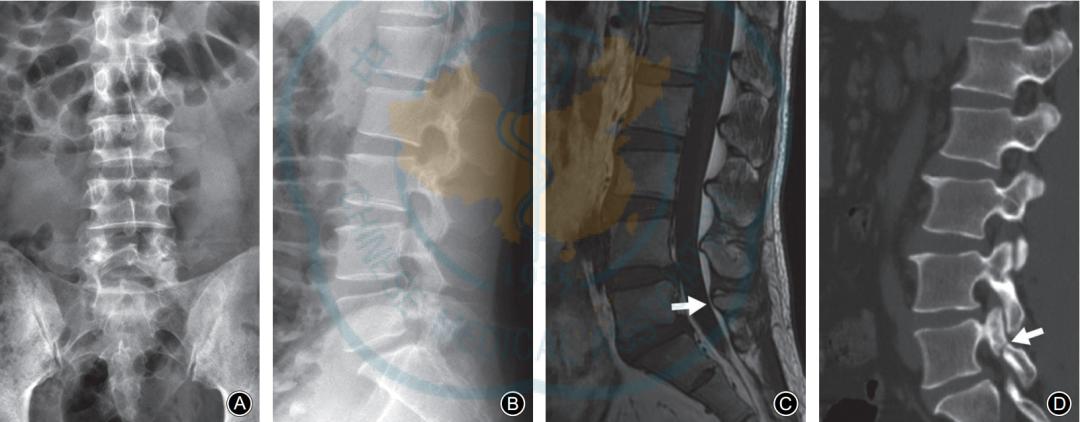

硬膜外脂肪增多症典型病例:男,50岁。A,B: 腰椎正位侧位X线片均无明显椎弓峡部裂征象; C: 腰椎MRI正中矢状面T1WI示L5棘突基底部(虚线剪头) 与硬膜之间出现脂肪高信号带, 伴有L4椎板腹侧弧形脂肪增多 (实线箭头)压迫硬膜。